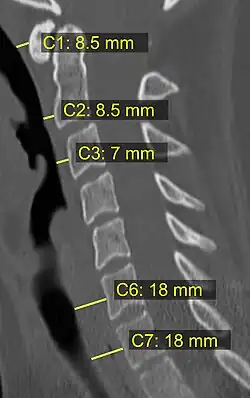

On CT scan or X-ray, a cervical fracture may be directly visualized. In addition, indirect signs of injury by the vertebral column are incongruities of the vertebral lines,[7] and/or increased thickness of the prevertebral space:[8]

8. ^ a b Rojas CA, Vermess D, Bertozzi JC, Whitlow J, Guidi C, Martinez CR (January 2009). "Normal thickness and appearance of the prevertebral soft tissues on multidetector CT". AJNR. American Journal of Neuroradiology. 30 (1): 136–141. doi:10.3174/ajnr.A1307. PMC 7051716. PMID 19001541.